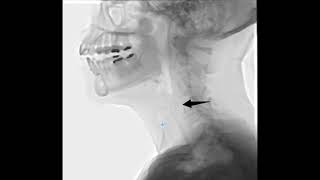

Disfagia mecánica provocada por osteofitos de columna cervical